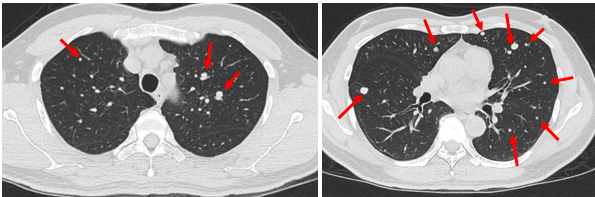

Hình ảnh Cắt lớp vi tính lồng ngực (04/2023):

Hình 6: Hình ảnh nhiều nốt mờ rải rác ở nhu mô 2 phổi, nốt lớn nhất có đường kính 9 mm (mũi tên đỏ). Số lượng tổn thương giảm so với CT 6/2022.